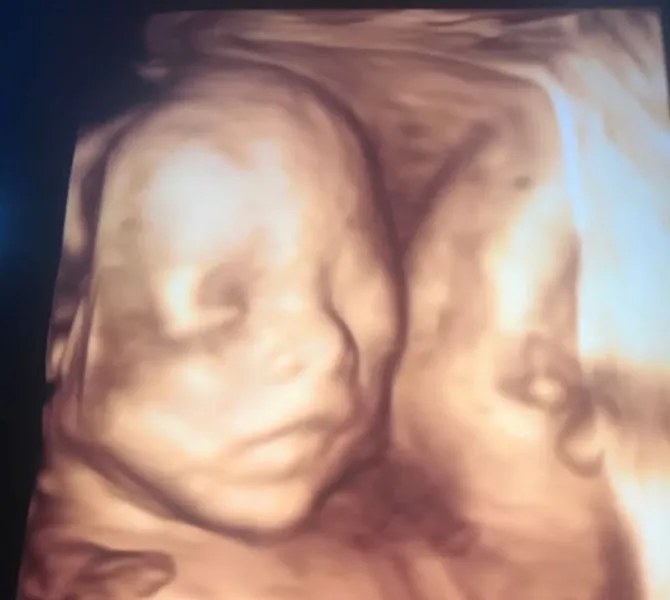

Fairuz selalu ditemani sang suami kontrol ke dokter. © Instagram/fairuzarafiqUntuk memeriksakan kesehatan janinnya, Fairuz pun rajin kontrol ke dokter kandungan. Di usia kandungannya saat ini, Fairuz pun memutuskan untuk menjalani USG 4 Dimensi. Melalui USG ini, wajah dan tubuh calon bayi akan terlihat lebih jelas dibandingkan USG biasa.

Beruntung, saat menjalani USG, wajah sang calon bayi terlihat sangat jelas. Dalam foto USG tersebut, ia tampak menghadap ke depan. Fairuz pun menggambarkan rasa bahagianya dengan menuliskan caption penuh haru.

Hasil USG Fairuz terlihat sangat jelas. © Instagram/fairuzarafiq"ALLAHU AKBAR... ALLAHUMMA SHALLI ‘ALAA SAYYIDINAA MUHAMMAD WA’ALAA AALI SAYYIDINAA MUHAMMAD.... Haiiii nak sehat2 ya kamu.. baru 5bulan udah kasih tahu mukanya ke mommy daddy gemeees... semoga selalu dalam lindungan ALLAH ya nak..aamiin.... #5monthspregnant" tulis Fairuz di akun Instagram pribadinya.